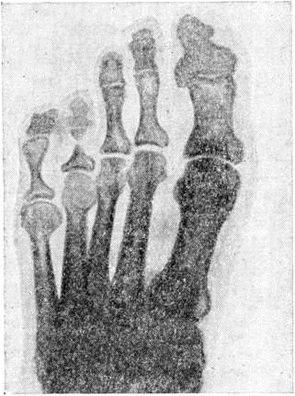

Рентгенодиагностика. При Лепра поражаются главным образом кости дистальных отделов конечностей. Для лепроматозного типа (LL) основными рентгенологическое признаками являются единичные или множественные очаги специфической воспалительной деструкции (лепромы) и нервно-трофические изменения, характеризующиеся атрофией, остеопорозом (смотри полный свод знаний) и рассасыванием костной ткани; лепромы чаще локализуются в губчатом веществе, реже в корковом веществе фаланг, пястных и плюсневых костей (рисунок 6). При разрушении ими суставных поверхностей происходит смещение дистально расположенных костей с образованием подвывиха или вывиха.

Рис. 2. | ||

Рис. 3. | ||

Рис. 4. | ||

При туберкулой дном типе (ТТ) очаговая деструкция костной ткани встречается довольно редко. Явления остеолиза (смотри полный свод знаний) как следствия нервно-трофических и сосудистых нарушений наблюдаются при всех типах Лепра, сопровождающейся полиневритами. Вначале эти изменения проявляются сглаженностью ногтевых отростков, расширением каналов, питающих кость, а в более поздних стадиях — ведут к мутиляции фаланг кистей и стоп. Концентрическая атрофия фаланг, являющаяся одним из характерных признаков Лепра, вызывает своеобразную деформацию костей в виде шахматной пешки (рисунок 7).

Резорбция костей может вести к патологический переломам, подвывихам, вывихам, анкилозам, частичному или полному отторжению костей (рисунок 8). Изменения в костях стоп обычно более выражены вследствие присоединения остеомиелита, вызывающего секвестрацию, деструкцию костей, и ведут к глубокой инвалидности больного. Встречаются также периоститы и гиперостозы плюсневых, метакарпальных, реже длинных трубчатых костей предплечий и голеней.